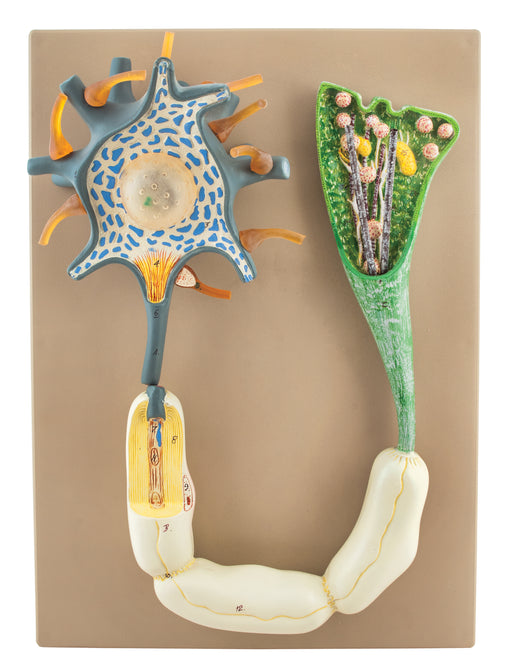

Neuron

Magnified more than 2500 times and fully three-dimensional, a neuron model is depicted in its natural setting. With the membranous envelope cut awa...

View full detailsAM16054 -

Neuron L.S.

This model showing neuron end and structure of nerve fiber. Mounted on base. Supplied with English Key Card. Size 42 x 30 x 7 cm approx. Weight 855...

View full detailsAM16053 -